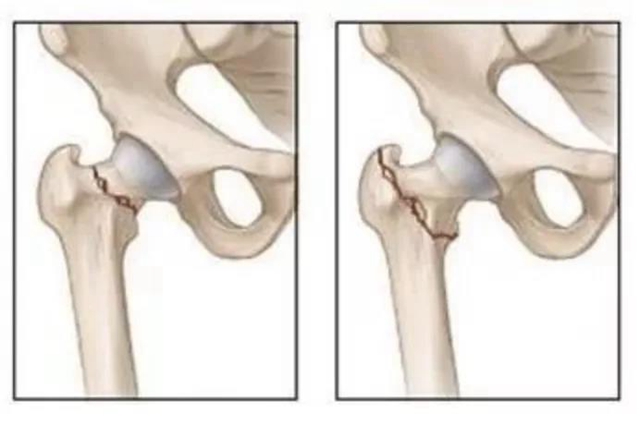

髋部骨折,是老年患者最常见的骨折之一,又称“人生最后一次骨折”。文献报道,老年髋部骨折1个月的死亡率为10%,4 个月为20%,1年为30%。

手术治疗是改善老年髋部骨折患者功能、提高生存率的首选方法,目前老年髋部骨折的手术方法已相当成熟,对于股骨颈骨折选择行关节置换治疗,对于粗隆间骨折,选择行微创内固定治疗,治疗成功率很高。